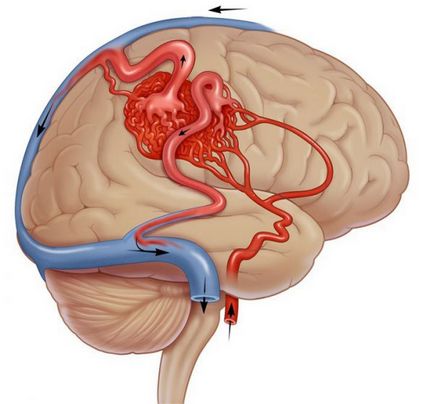

Arteriovenosus malformáció (AVM) egy komplex összefonódása abnormális artériák és vénák kapcsolódik egymáshoz útján egy vagy több vegyület az úgynevezett fisztulák vagy söntök. Ez összefonódása fejlődési hívják a kernel. Normális esetben, a vér az artériákban a rendszer nagy nyomás alatt. Aztán, ahogy a folyosón keresztül a kapilláris-ágyon a vénás rendszer, van egy lassú vérnyomásesést. Amikor AVM kapilláris ágy nem áll rendelkezésre, a vér az artériákban a vénákban közvetlenül belép a rendszerbe.

A legtöbb esetben van egy intenzív véráramlást a AVM kernel, de nem ismert, hogy pontosan mi okozza. Az egyik hipotézis, a vér az artériákban a rendszerbe a vénák miatt a különbség a nyomás. Amikor áthalad egy artériás vér kapilláris ágy AVM etetés a szövet elveszti a kívánt mennyiségű vért.

Idővel, intenzív a vér áramlását a lényege a fejlődési rendellenesség vezet bővítése az érintkeztetés az artériák és vénák (dilatáció). Ez gyengíti az erek, így hajlamos a törés és vérzés. A szállítási artériák hajlamosak a aneurizmák, amely végül vezethet törés és vérzés az agyban.

Fokális neurológiai deficit nélkül vérzés jeleit jelentettek 1-40% -ánál. Általában ezek a tünetek társított átirányítását a vér áramlását a AVM, és a kapott vérellátás hiánya, hogy az agy. Azonban nincs jó okunk azt hinni, ez a jelenség a klinikailag fontos mechanizmus.